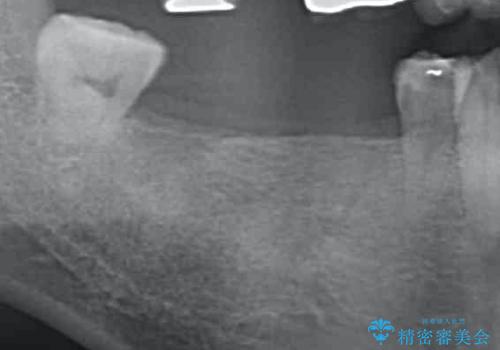

失った奥歯をインプラントで機能回復

- 3本失った奥歯の機能回復するために、インプラント治療を希望され来院されました。

インプラント以外にとりうる機能回復の代替手段は「入れ歯」、となります。

よりしっかりと噛むことのできるインプラントによる治療を進めていくこととなりました。